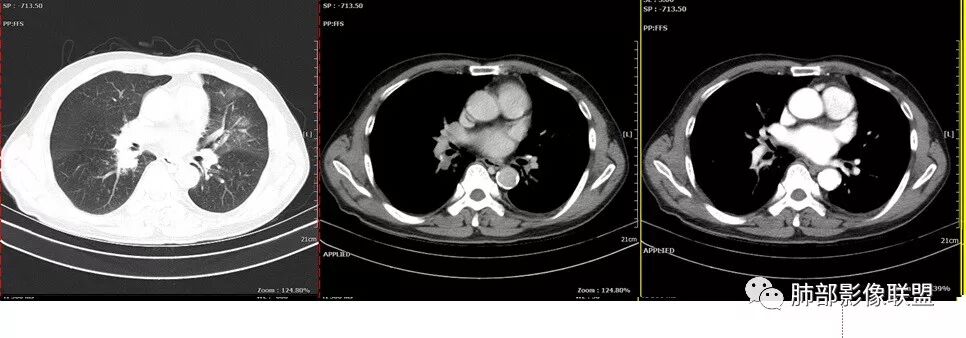

老年男性,反复咳嗽咳痰十余年,加重伴发热5天,胸痛2天。既往有糖尿病病史。白细胞不高,肝功能受损,CRP及igE明显增高。左肺上叶大片磨玻璃影伴局部实变,支气管通畅,右肺下叶背段近端支气管旁不规则实性结节,轻度均匀强化,背段支气管受压变窄,纵隔及双肺门多发淋巴结肿大并钙化。考虑左上肺感染性病变,先抗感染复查,继续查病原体。右下肺背段结节建议经TBLB活检,排外肿瘤。

患者中老年男性,发热,咳嗽5天,胸痛2天。慢性咳嗽,咳痰10余年,目前出现活动后胸闷气短,有基础糖尿病、高血压病史,查白细胞正常,CRP增高,IGE增高,CEA轻度增高。胸部CT:左肺上叶片状密度增高影,边界清楚,内血管穿行,呈蜂窝网格状,内有磨玻璃影,部分支气管壁增厚,部分有扩张,部分有近段粗细不均;右肺下叶可见一结节影,有凹陷,有膨隆,似有结节感,右侧肺门淋巴结肿大,纵隔多发淋巴结肿大、部分伴有钙化。综合考虑恶性病变,左上肺粘液腺癌可能,右下肺小细胞癌?两源论考虑:左上肺粘液腺癌或粘膜相关性淋巴瘤?右下肺结核球伴肺门淋巴结肿。

左肺上叶病灶长轴与支气管走形一致,提示沿支气管分布病变,倾向于炎性,大家可能怀疑这个病例是来源于胸膜下为主的,胸膜下来源首先整体是来源于胸膜下,与胸膜下之间没有间隙,而这例与胸膜下有间隙。而且这个病变是沿支气管朝外蔓延的,而胸膜下来源的是朝内蔓延的,唯一给我们错觉的是靠近纵隔胸膜这个地方有问题。但是靠近纵隔胸膜这个位置实变不是靠近胸膜实变,它边缘收缩的,没有膨隆的迹象。我们看到里面支气管直达远端稍扩张,是以中央间质为主、小叶间隔朝外蔓延,有间质也有实质病变,走向是沿中央间质方向走的,我个人倾向炎性病变。    问题是右下叶病灶怎么解释?右隔上、右肺门各有一个结节。这个病人有急性咳嗽、胸痛的病史,还有糖尿病病史,周围渗出比较明显,应该警惕炎性病变,要警惕克雷伯杆菌、结核、金葡菌霉菌,因为糖尿病人经常好发这些病菌感染。那么右下叶病变怎么考虑?能不能一元论?    左肺病灶是一个急性渗出为主的病变,一个急性感染的迹象;右肺下叶背段结节,没有看到支气管,增强图支气管壁增厚,局部小结节,呈分叶状,支气管堵塞,没有粘液栓样指套样改变,但是里面有强化,我倾向于癌,其次待排结核。我还是倾向于癌的可能性,恶性可能性大一些,可惜我看不到支气管腔内。还考虑有没有淀粉样变性的问题,弥漫钙化灶最常见的一个是结核,另一个是淀粉样变性。叶段支气管壁有弥漫增厚的迹象。所以淀粉样变性跟结核都要考虑。